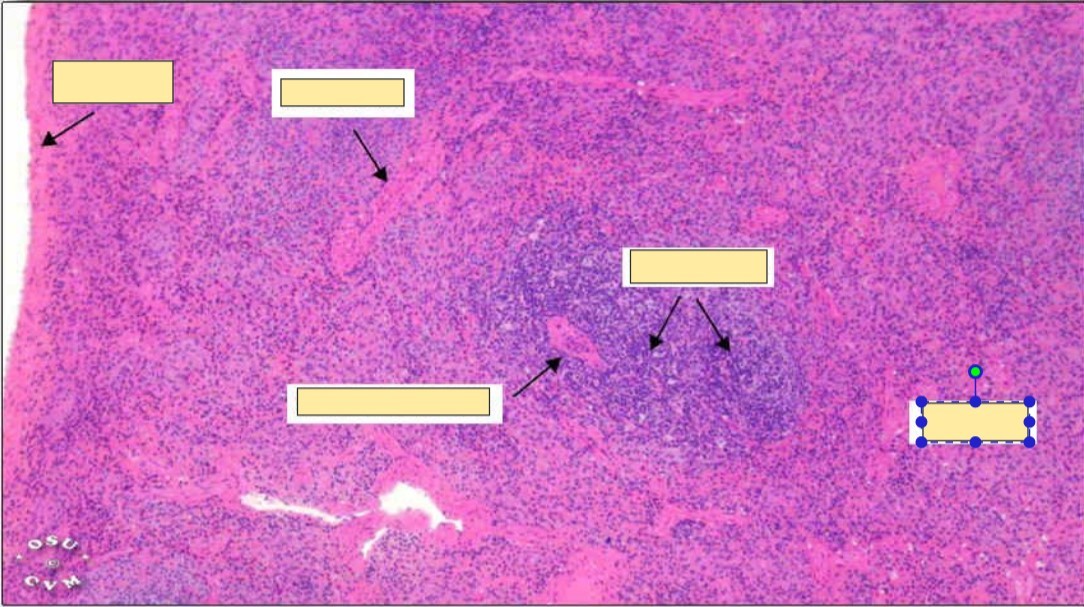

This shows

______________ of the _______ of lymphoid follicles.

The arteriolar wall is ______ and their ______ is narrowed.

A

Hyaline degeneration

Central arterioles

Thickened

Narrowed

The ________ & ________ also show hyalinosis

splenic capsule

Trabeculae

hyalinosis of spleen

capsule

central arteriole

white pulp

red pulp